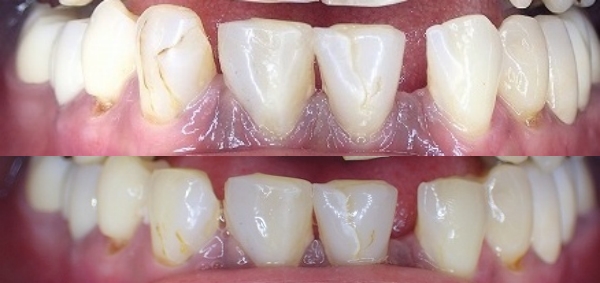

上が本来あるべき咬み合わせ

下が奥歯がないので前歯の上下で咬む習慣

歯の切端が削れています。

この場合は大きくレジン充填がしてありますので

これ以上レジン充填をすると、歯が崩壊するリスクが

高くなると思われます。